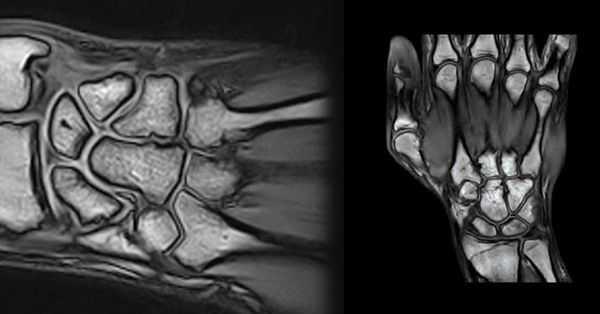

МРТ сухожилий запястья в продольной проекции в норме

На рисунке в аксиальной проекции показаны сухожилия в проксимальном отделе запястья. Сухожилия мышц-разгибателей проходят под удерживателем разгибателей, а сухожилия сгибателей на этом уровне запястья расположены проксимальнее удерживателя сгибателей. На соответствующем МР-срезе все сухожилия создают сигнал низкой интенсивности. На рисунке в аксиальной проекции показаны сухожилия в запястном канале. Сухожилия глубокого сгибателя пальцев направляются к мизинцу, безымянному, среднему и указательному пальцам параллельно друг другу (от медиальной стороны к латеральной). Из сухожилий поверхностного сгибателя пальцев два глубоких сухожилия направляются к среднему и безымянному пальцам и два поверхностных сухожилия проходят к мизинцу и указательному пальцам. Сухожилие длинного разгибателя большого пальца проходит над сухожилием короткого лучевого разгибателя запястья (КЛуРЗ). На соответствующей рисунку аксиальной МРТ показаны сухожилия в запястном канале. Обратите внимание на феномен «магического угла» на ДРБП в месте его прохождения над КЛуРЗ. Сухожилие находится под углом 55° к главному магнитному полю, что приводит к потере нормального низкоинтенсивного сигнала. На первой из шести отобранных аксиальных МР-томограмм показан ход сухожилий и их отношение к окружающим костным структурам. Удобным костным ориентиром служит бугорок Листера, разделяющий II и III каналы разгибателей. Удерживатель разгибателей удерживает сухожилия разгибателей в шести отдельных каналах. Срединный нерв имеет округлую форму и лежит кнаружи и латеральнее сухожилий сгибателей пальцев. Обратите внимание на феномен «магического угла» на ДРБП в месте ее пересечения с КЛуРЗ. Удерживатель сгибателей огибает запястный канал от бугорка ладьевидной кости до крючка крючковидной кости. Его поверхностные волокна образуют крышу канала Гийона. Удерживатель сгибателей прикрепляется к гребню кости-трапеции с латеральной стороны и крючку крючковидной кости — с медиальной. При трехмерной КТ реконструкции с наложением мягких тканей показаны границы анатомической табакерки: длинный разгибатель большого пальца (III канал), пересекает запястье с медиальной стороны к латеральной над сухожилиями короткого и длинного лучевых разгибателей запястья (II канал), образуя заднюю границу, тогда как сухожилия длинной мышцы, отводящей большой палец и короткого разгибателя большого пальца (I канал) образуют переднюю границу. Через анатомическую табакерку проходят лучевой нерв и его поверхностная ветвь, а также одноименные артерия и вена. На МР-томограмме анатомическая табакерка показана в аксиальной проекции. При трехмерной КТ-реконструкции с наложением мягких тканей показан мышечно-сухожильный перекрест короткого разгибателя большого пальца и длинной мышцы, отводящей большой палец, с сухожилиями длинного и короткого лучевых разгибателей запястья, продолжающийся в дистально-латеральном направлении непосредственно проксимальнее удерживателя разгибателей. На аксиальных МР-томограммах их сложное взаимное расположение показано на поперечном срезе. На нижней правой МР-томограмме показан дистальный отдел предплечья: короткий разгибатель большого пальца и длинная мышца, отводящая большой палец, лежат кнаружи и немного кзади от сухожилий короткого и длинного лучевых разгибателей запястья. На нижней левой и верхней правой МРТ короткий разгибатель большого пальца и длинная мышца, отводящая большой палец, пересекают сверху длинный и короткий лучевые разгибатели запястья и располагаются на латеральной поверхности лучевой кости. На верхней левой МР-томограмме—наиболее дистальном из этих срезов, на уровне бугорка Листера, перекрест заканчивается, и сухожилия занимают свое положение на запястье.

Первая из 20 последовательных Т1-взвешенных томограмм запястья в продольной проекции с направлением срезов от локтевой (медиальной) стороны к лучевой (латеральной). Сухожилие ЛоРЗ пересекает дистальный отдел локтевой кости в локтевой борозде ЛоРЗ. Мышца, отводящая мизинец—самая медиальная и передняя мышца гипотенара. Гороховидно-пястная связка соединяет гороховидную кость с V пястной костью. Она прилежит к гороховидно-крючковидной связке (следующая томограмма). Хорошо виден гороховидно-трехгранный суставной карман. Мышцы гипотенара менее прочные в области отхождения их от удерживателя сгибателей. Сухожилие локтевого сгибателя запястья прикрепляется к гороховидной кости. Локте-трехгранная связка отходит от ладонной лучелоктевой связки и прикрепляется к ладонной поверхности трехгранной кости. Локтевые нерв и артерия проходят в канале Гийона латеральнее и дистальнее гороховидной кости. Выступает крючок крючковидной кости. Треугольный хрящевой диск (ТХД) визуализируется в виде диска с низкоинтенсивным сигналом между головкой локтевой кости и трехгранной костью. Ладонная и тыльная лучелоктевые связки вместе с ТХД и прилежащими структурами образуют треугольный фиброзно-хрящевой комплекс. Внешние и внутренние связки иногда сложно выделить в качестве отдельных образований. Указатели направлены к визуализируемым связкам или месту возможного обнаружения связки. Тыльная межзапястная связка—основная связка, стабилизирующая тыльный отдел запястья, но визуализируется только на ограниченном участке. Сухожилия поверхностного и глубокого сгибателей пальцев проходят под горизонтально расположенным удерживателем сгибателей. Сухожилия разгибателя пальцев проходят через IV канал разгибателей и фиксируются удерживателем разгибателей. На ладонной поверхности можно увидеть пучки лучеладьевидно-локтевой и короткой лучеполулунной связок. На задней поверхности можно увидеть тыльную лучезапястную связку, отмечена область тыльной межзапястной связки. Характерный наклон в ладонную сторону дистального отдела лучевой кости обусловлен тем, что тыльный край лучевой кости расположен более дистально, чем ладонный (12°). Центральная ость запястья образована основанием III пястной кости, головчатой и полулунной костями, а также полулунной ямкой лучевой кости. Сухожилие разгибателя указательного пальца—самое латеральное сухожилие IV канала разгибателей. Сухожилие мышцы, противопоставляющей большой палец, на этом срезе отходит от удерживателя сгибателей. Срединный нерв расположен поверхностнее сухожилия длинного сгибателя большого пальца и глубже удерживателя сгибателей. Длинная лучеполулунная связка отходит от лучевой кости непосредственно латеральнее лучеладьевидной и короткой лучеполулунной связок. Сухожилие длинного разгибателя большого пальца лежит медиальнее бугорка Листера и в дистально-латеральном направлении на пути к большому пальцу пересекает сухожилия длинного и короткого лучевых разгибателей запястья. На этом срезе визуализируются сочленения трапециевидной, головчатой и ладьевидной костей между собой. Сухожилие длинного сгибателя большого пальца проходит под локтевым нервом непосредственно медиальнее сухожилия лучевого сгибателя запястья. Сухожилие короткого лучевого разгибателя запястья (КЛуРЗ) прикрепляется к основанию III пястной кости. Сухожилие лучевого сгибателя запястья проходит поверхностнее бугорка ладьевидной кости и прикрепляется к основанию II пястной кости. Лучеладьевидно-головчатая связка отходит от края ладонной поверхности лучевой кости. Сухожилие лучевого сгибателя запястья проходит поверхностнее бугорка ладьевидной кости и прикрепляется к основанию II пястной кости. Сухожилие короткого лучевого разгибателя запястья (КЛуРЗ) пересекает тыл запястья и прикрепляется к тыльной стороне основания III пястной кости. Наиболее латеральный отдел лучеладьевидно-головчатой связки иногда называют лучевой коллатеральной связкой. Сухожилие длинного лучевого разгибателя запястья (ДЛуРЗ) пересекает тыл запястья и прикрепляется к основанию II пястной кости. Лучевая артерия, поверхностная ветвь лучевого нерва и латеральная подкожная вена руки проходят через анатомическую табакерку, ограниченную костью-трапецией, ладьевидной костью и шиловидным отростком лучевой кости. Сухожилия длинной мышцы, отводящей большой палец и короткого разгибателя большого пальца, образуют ладонный край анатомической табакерки, а сухожилие длинного разгибателя большого пальца формирует ее тыльный край. Сухожилия длинной мышцы, отводящей большой палец и короткого разгибателя большого пальца, образуют дистальный край анатомической табакерки после соединения непосредственно дистальнее I запястно-пястного сустава. Лучевая артерия разветвляется и продолжается в дистальном направлении, образуя глубокую ладонную дугу. Сухожилия длинной мышцы, отводящей большой палец и короткого разгибателя большого пальца соединяются в месте прикрепления к основанию I пястной кости.